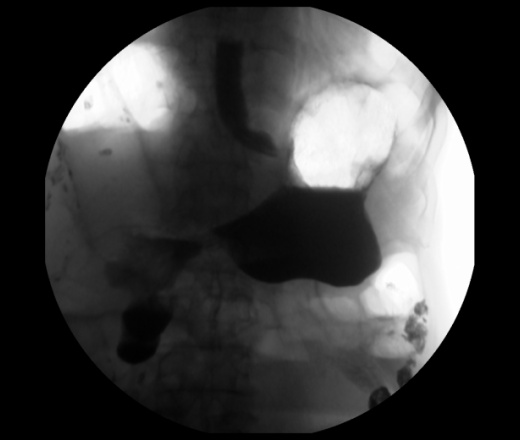

Мужчина 73 года. Жалобы на сниженный аппетит, слабость. Исследование выполенено через несколько дней после ирригоскопии. По результатам ЭФГДС гастрит.

Угол желудка развернут, ригиден. Стойкое циркулярное сужение антрального отдела.Перистальтики нет. Складки прослеживаются.

Эндофитный C-r антрального отдела.